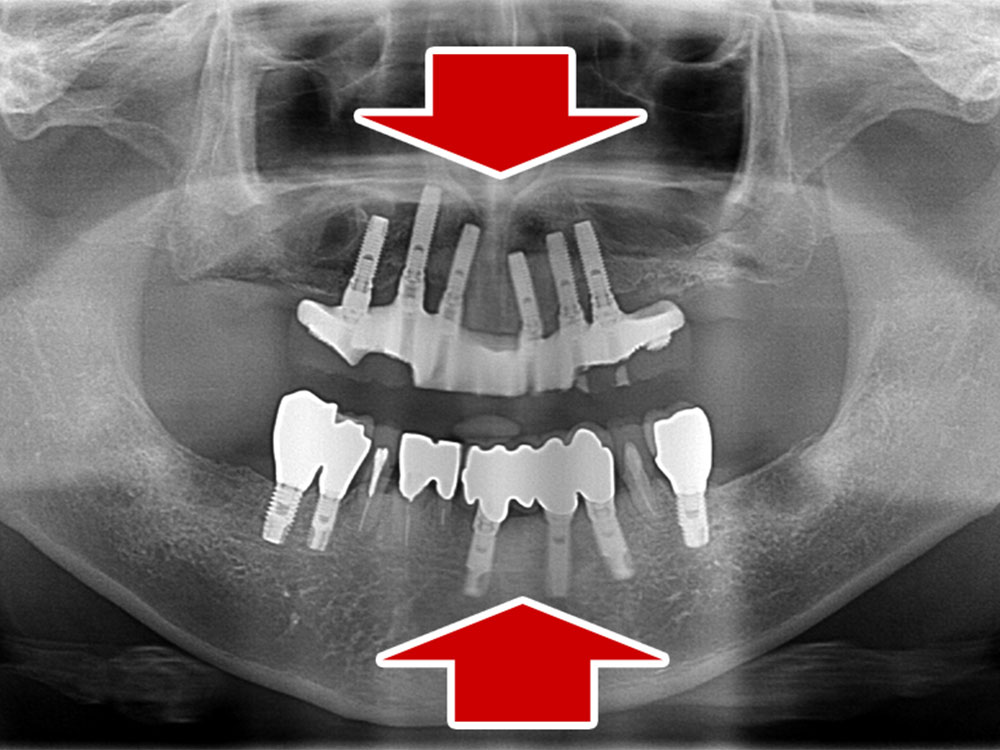

症例紹介

- 主訴

- 入れ歯が合わない。食べにくい。人生を豊かにしたい。

- 処置内容

- 上顎4本で12歯(オールオン4)、下顎4本5歯。

上下抜歯即時埋入、即時荷重(手術当日にインプラントの上に仮歯装着)

- 治療費用

- 上顎:約290万(税込)、下顎:約210万円(税込)

- 治療期間・通院回数

- 上顎:9か月/9回

下顎:6か月/7回

- リスク

- 術後の腫れ、痛み(ピークは3日後、1週間で軽減)

上部構造物、仮歯の破折、人工歯根脱落リスクがあります